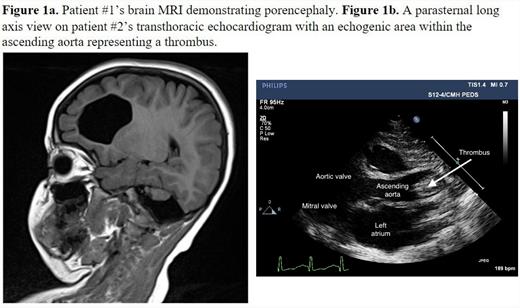

Patient #1 is an 8-year-old male with history of neonatal stroke, dense left hemiplegia, and cerebral palsy, who underwent whole exome sequencing due to MRI findings (Figure 1a). This identified an apparently homozygous variant in POMC, c.1154T>C

(p. Met385Thr)in exon 9. Both parents were confirmed to be heterozygous carriers. The patient was found to have a normal antigen of 62% and a severely low activity of <10%, suggesting a diagnosis of type II protein C deficiency. He is being considered for extended anticoagulation with a direct Xa or IIa inhibitor or a vitamin K antagonist.

Patient #2 was born at 34 weeks and presented immediately following birth with a large occlusive thrombus in the ascending to proximal aorta as well as left ventricular dysfunction and mitral regurgitation (Figure 1b). She was not a candidate for thrombectomy or catheter-directed tissue plasminogen activator (TPA) due to her age and procedural risks. She was given systemic TPA due to severe end organ dysfunction followed by unfractionated heparin (UFH). Due to neurological changes and intracranial hemorrhage (ICH), TPA and UFH were discontinued. Fresh frozen plasma and protein C concentrate were administered and UFH was resumed. Due to worsening ICH, UFH was again stopped, and she developed a left ventricular thrombus, impairing her systemic circulation. Her clinical status worsened, and she became unresponsive to resuscitation efforts, and passed away on DOL 16. Testing identified a protein C antigen and activity level of 10% and <15% respectively. This patient was found to have 2 variants in the PROC gene, c.30C>T (p. Phe10Phe), which is a variant of uncertain significance, and c.1019C>T (p. Thr340Met), which is known to be pathogenic.